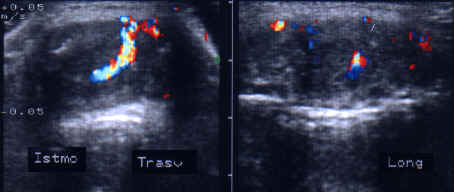

Femeie de 34 ani. Tiroida de dimensiuni normale, de

consistenta dura, cu suprafata neregulata si pseudonodulara, dureros la palpare.

Marginile lobilor sunt rau definite; structura este mult neomogena cu alternanta

de arii hipoecogene d e edem si altele hiperecogene, cu aspect pseudonodular.

Examene de laborator: moderat hipertiroidism; indicii de fiboza mult ridicati.

Aceeasi pacienta. Vascularizatie intraglandulara mult diminuata.